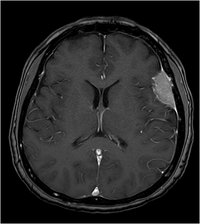

Konvexitätsmeningeom - T1 mit KM